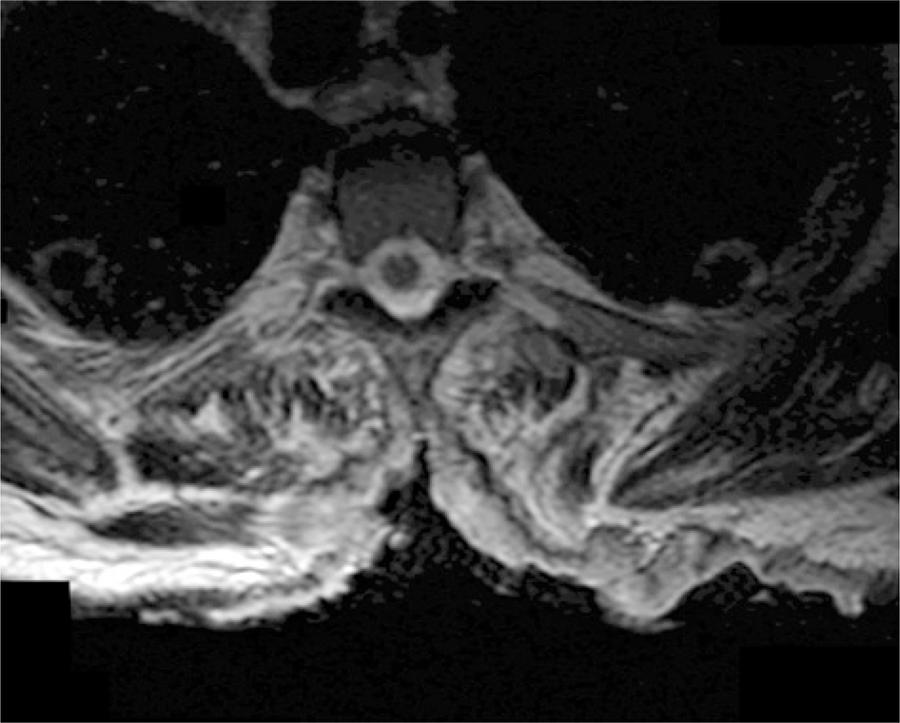

The patient had no known history of malignancy, immunosuppressive conditions, autoimmune disorders, exposure to communicable diseases, or travel outside of the United States. His vital signs were within normal limits. Physical examination revealed a 26cmx16cm ulcerative lesion spanning the T1 through T8 vertebral bodies with exposure of the spinous processes and paravertebral musculature, which was most prominent at the level of T5. The lesion contained punctate areas of bleeding, granulation tissue, and copious serous drainage. The boarders were clearly defined and without satellite lesions (). Other than pallor of the skin, the remainder of the physical examination, including a full neurological assessment, was unremarkable. In the emergency room, a computed tomography scan of the chest/abdomen/pelvis was performed and two individual punch biopsies of the ulcer bed were taken. The computed tomography scan showed erosion of the thoracic spinous processes but no evidence of metastatic disease. A complete blood count revealed a hemoglobin and white blood count of 4.6g/dL and 6.9 cells x 103/µL, respectively. On admission the patient was transfused for his symptomatic anemia and started on ferrous sulfate.